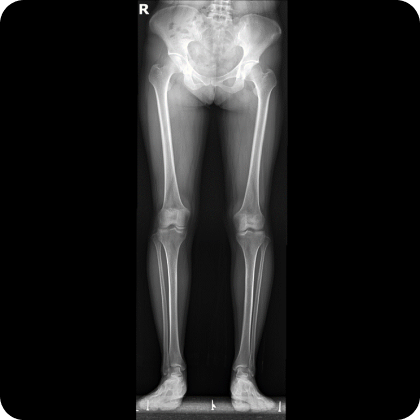

▲ 치료 전 (2016년 1월 21일)

▲ CTA 5개월 착용 (2016년 6월 29일)

▲ CTA 9개월 착용 (2016년 10월 29일)